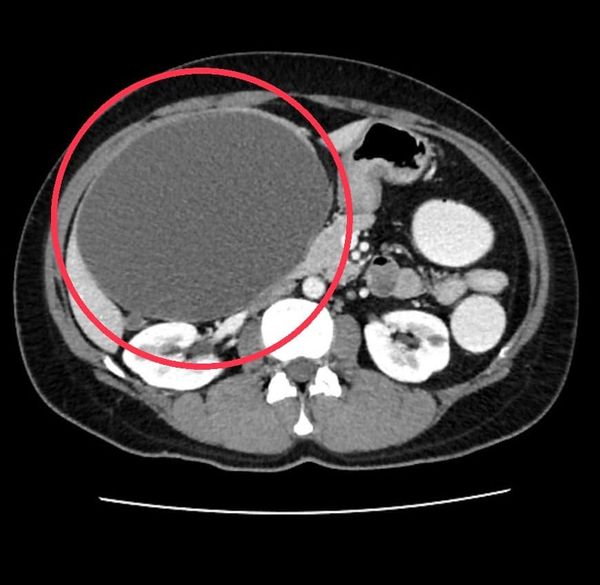

ថៃ៖ កាលពីពេលថ្មីៗនេះ លោកវេជ្ជបណ្ឌិត Arak Wongvorachat ប្រធានមន្ទីរពេទ្យ Sichon ខេត្ត Nakhon Si Thammarat បានបង្ហោះសារតាមរយៈ Facebook លោក Arak Wongworachat រៀបរាប់ពីករណីដែលបានរកឃើញនៅក្នុងអ្នកជំងឺម្នាក់ ដែលមាន ដុំគីសធំទំហំ ២០ សង់ទីម៉ែត្រនៅជាប់ថ្លើម។

បើតាមការរៀបរាប់របស់លោកវេជ្ជបណ្ឌិតយ បានឲ្យដឹងថា អ្នកជម្ងឺអាយុ ៤៤ឆ្នាំ មានអាការៈហើមពោះ ណែនពោះ អស់រយៈពេលជាង ១ឆ្នាំ ដោយព្យាបាលខ្លួនឯងទៅតាមអាការៈ។ ក្រោយមកទៀត ពោះក៏ចាប់ផ្តើមធំឡើងៗ ក្នុងរយៈដ៏លឿន ដូចអ្នកមានផ្ទៃពោះ ហើយមានអារម្មណ៍តានតឹង និងតឹងណែនរាល់ដងនៅពេលដែលត្រូវសម្រាន្តកន្លែងរាបស្មើរ ដូច្នេះទើបលោកសម្រេចចិត្តទៅពិនិត្យនៅមន្ទីរពេទ្យមួយកន្លែង ក្រោយលទ្ធផលចេញមកបង្ហាញថា ឃើញមានដុំគីសធំមួយនៅជាប់នឹងថ្លើម។